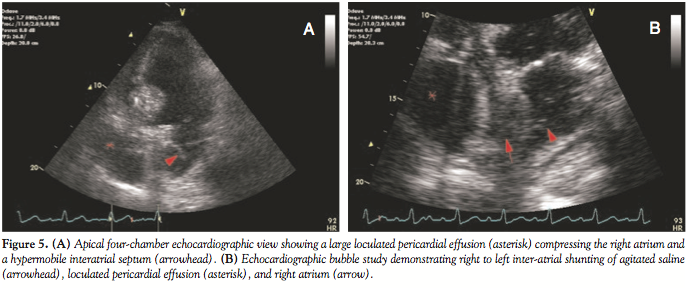

The patient was transferred to the coronary care unit, where intravenous vasopressors and fluids were weaned off and hemodynamic measurements stabilized. However, he continued to require supplemental oxygen due to hypoxia with pulse oximetry of 85% on 4 liters oxygen by nasal cannula. Physical examination did not reveal signs of fluid overload or congestive heart failure. Repeat echocardiogram demonstrated a large, localized pericardial effusion measuring 8 cm in diameter, surrounding and compressing the right atrium; hypermobile interatrial

septum; and a right to left shunt through a patent foramen ovale by color flow Doppler and agitated saline injection (Figures 5A and 5B). Repeat angiography confirmed TIMI 3 flow in the SVG and distal right coronary artery with no angiographic evidence of persistent perforation. Serial bedside echocardiograms demonstrated no change in the size of pericardial effusion with persistent right to left inter-atrial shunting of blood. However, since the patient continued to exhibit significant hypoxia requiring